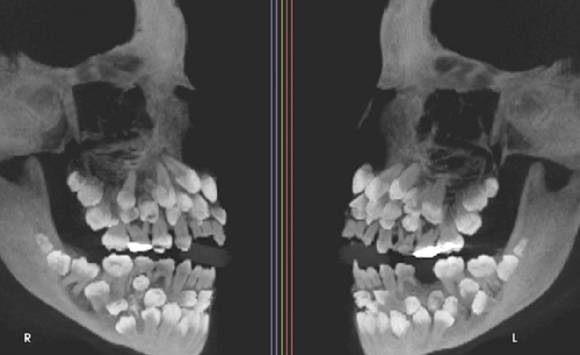

이 소녀는 유치 1개를 발치하기 위해 병원을 찾았다가 엑스레이 촬영 결과 예상치 못한 사실을 발견했다. 유치 18개, 영구치 32개, 과잉치 31개 등 총 81개의 치아가 그의 입 안에 존재했던 것이다.

의료진은 이를 '다발성 과잉치증(multiple hyperdontia)'으로 진단했다. 이는 정상 치아 수(성인 기준 32개)를 초과해 여러 개의 추가 치아가 존재하는 선천성 이상으로, 통상 1~2개의 과잉치만 발견되는 경우가 많다. 하지만 이처럼 30개가 넘는 과잉치가 한 사람에게서 확인된 사례는 전 세계적으로도 극히 드물다.

!['치아 81개'를 가진 사례가 학계에 보고됐다. 사진은 소녀의 엑스레이. [사진=미국 치과교정·악안면외과학회지(AJO-DO)]](https://img1.daumcdn.net/thumb/R658x0.q70/?fname=https://t1.daumcdn.net/news/202507/17/inews24/20250717110634192jkmv.jpg)